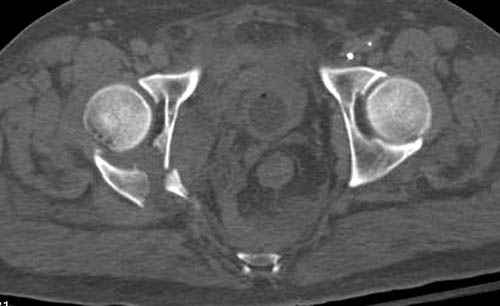

Дополнительно имеется перелом ацетабулума: задняя

колонна с полупоперечным переломом, и переломы костей лица.

На седьмой день зафиксирован перелом ацетабулума через задний доступ. Перед операцией для профилактики DVT, IVC фильтер, также получает Lovenox.

По снимку создается впечатление о высоком поперечном переломе, задней колонны, стенки; почему не пользовались *magic screw*?